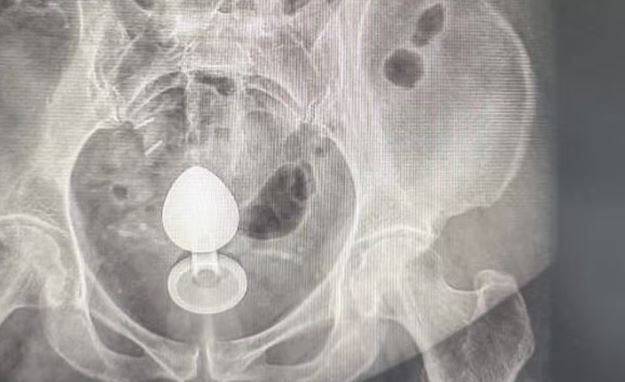

Uma mulher precisou ser internada após um plug anal ficar retido no intestino. O objeto havia sido introduzido por ela com a intenção de aliviar a constipação, mas acabou “subindo” e não pôde ser retirado de forma manual.

“Ela contou que colocou o objeto no ânus por volta das 7h. Pouco mais de duas horas depois, ao sentar, percebeu que ele havia subido e precisou buscar atendimento médico”, explicou o especialista.

O intestino pode “sugar” objetos devido aos movimentos peristálticos — contrações naturais responsáveis pelo funcionamento do órgão — ou pela formação de um efeito de vácuo na região do reto.